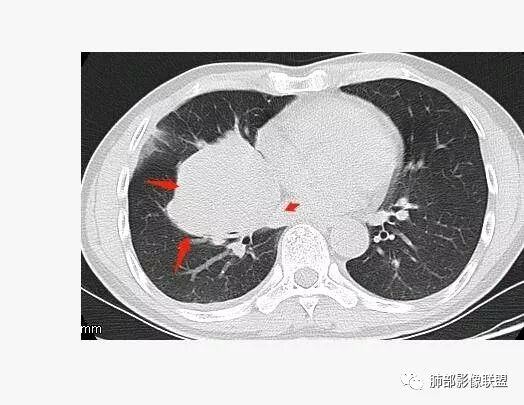

南边:深分叶、大肿块

南边:主体在下叶前基底段

南边:边缘膨隆

南边:中叶、下叶背段支气管推移

南边:中叶支气管腔内似有粘液栓,外侧段有炎性病变

南边:有老师问为啥考虑中叶支气管受压?不是支气管来源的?

1、主体病灶在下叶

2、支气管腔还在,有移位

但是现在的片显示,其主体在下叶,中叶支气管壁由下朝上有推移

南边:下叶的支气管受压后移、变形

南边:病灶边界清,提示侵袭性弱,膨胀生长为主;这时候我们提示病灶不应该是支气管关系密切,提示间叶来源或胸膜来源

深分叶,警惕恶性